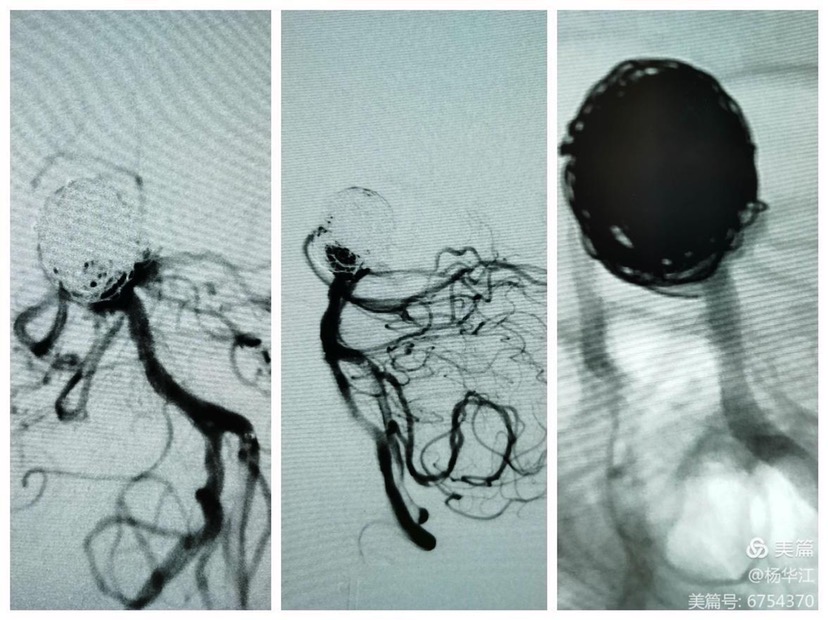

CTA及DSA显示:颈内动脉床突上段巨大动脉瘤(最大径25.6mm);基底动脉尖大动脉瘤(最大径20.3mm),瘤颈宽11mm,累及双侧大脑后动脉、小脑上动脉,右侧大脑后动脉自瘤体侧后方发出。

4.0x35pipeline经成襻的phenom导管缓慢送人右侧大脑后动脉远端,锚定,缓慢半释放至基底动脉中上段。

然后填圈至动脉瘤中、上部致密填塞,下部近分支处疏松填塞,同时释放左侧EP2支架,尾端紧贴pipeline侧方呈T形放置。最后稍推拉完全pipeline至基底动脉中下段。(这是本次手术有瑕疵的地方,尾端覆盖基底动脉稍长了一些,与我们测量计算误差有关)

术后即刻造影显示瘤体中上部已完全不显影,仅下部可见造影剂,基底动脉各分支显影良好。

DynaCT显示pipeline打开贴壁良好。